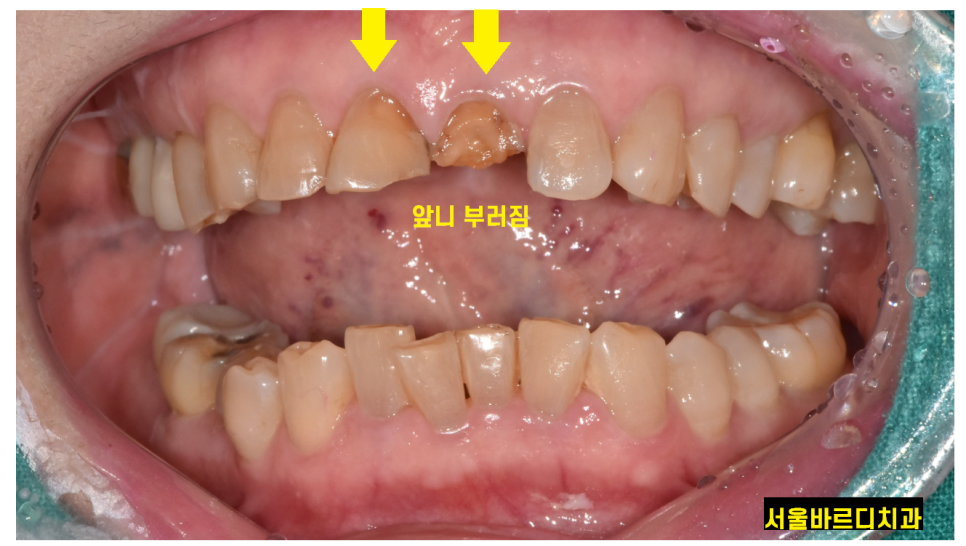

앞니 치료는 심미적인 이유로 브릿지를 추천하기도 합니다.

앞니 뼈가 얇아 고난이도 수술 부위이기도 하고

시간이 지나 앞니 뼈가 꺼지면 안예쁜 경우가 있거든요~

그리고 앞니 상실을 몇달간 겪기에는

일상 생활이 힘들어지기에ㅠㅠ